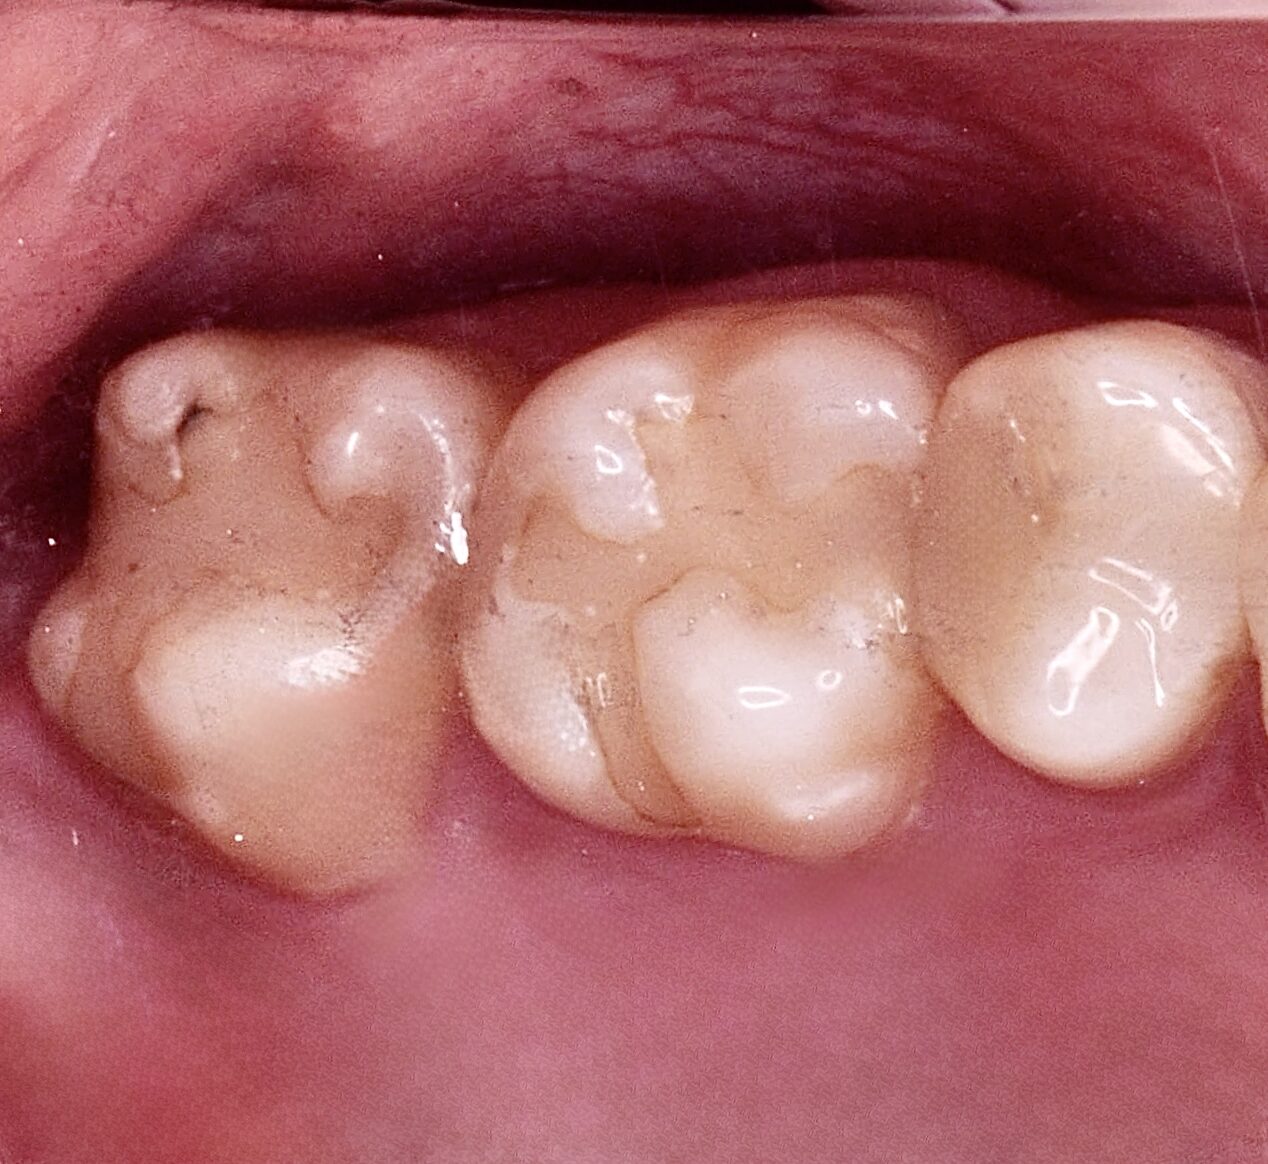

右下7ダイレクトボンディング

虫歯の治療希望で、右下の旧充填物と感染歯質の除去。 ラバーダム下で、プラークアウトと歯面処理を行い、接着操作とレジン充填を行った。 咬合調整はほぼなく研磨で終了。